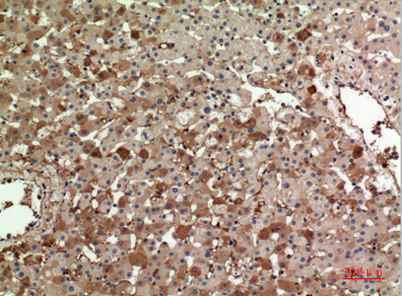

Product name: ApoA-I rabbit pAb

Dilutions: Western Blot: 1/500 - 1/2000. IHC-p: 1/100-1/300. ELISA: 1/20000. Not yet tested in other applications.

Immunogen: The antiserum was produced against synthesized peptide derived from the Internal region of human APOA1. AA range:81-130